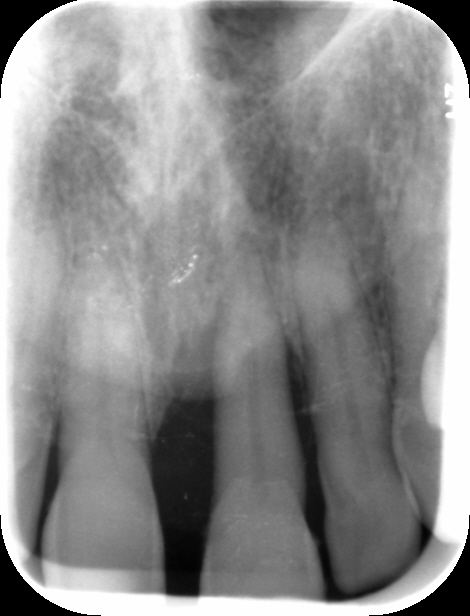

Patient InformationA patient presented with severe mobility of tooth 21.

Medical history revealed that the patient was a non-smoker, had no diabetes, and no relevant systemic conditions. Dental history indicated previous trauma to tooth 21. Clinical examination showed Grade III mobility of tooth 21, localized severe periodontal destruction around the tooth, chronic periodontitis, bleeding on probing (BoP) of 10%, and the presence of calculus in the lower jaw. CBCT examination demonstrated complete buccal bone dehiscence around tooth 21 with limited remaining bone support. Therefore, extraction of tooth 21 was indicated.